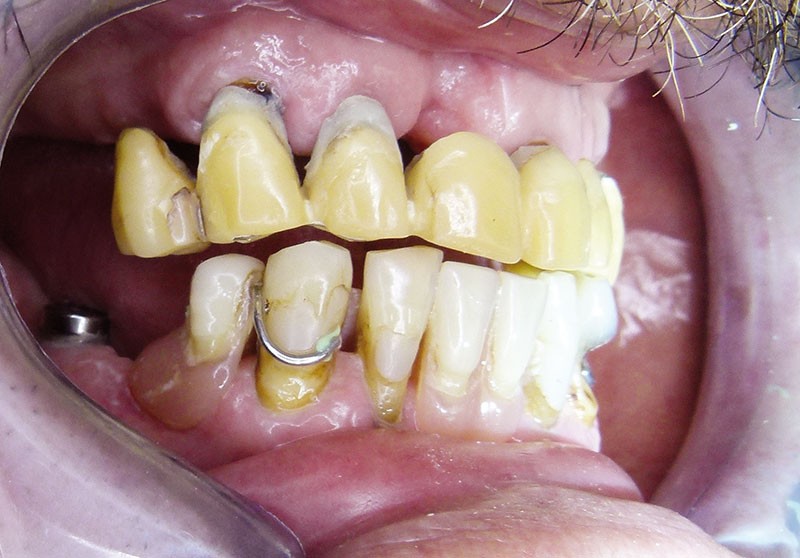

Monsieur L… se présente en décembre 2012 pour une demande de réhabilitation complète de sa cavité buccale. Il est âgé de 65 ans. Il présente un bon état de santé générale, sans pathologie restrictive. En revanche, son état bucco-dentaire est pour le moins problématique … Il est porteur de prothèses provisoires qui se sont délitées avec le temps. Plusieurs implants ont été mis en place auparavant, à la mandibule. Les restaurations d’usage n’avaient jamais été réalisées … (fig. 1 et 2).